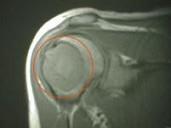

问题 成骨细胞瘤的MRI影响中,哪项错误()

选项 A.肿瘤内的钙化,骨化部分在TWI上为低到中等信号,TWI上为高信号 B.肿瘤内的骨化,钙化部分在各扫描序列上均呈低信号 C.病灶周围的骨髓和软组织内出现反应性充血水肿,表现为短T1短T2信号 D.可清楚显示骨质中断和局部软组织肿胀 E.发生于脊椎的病变如向椎管内扩展,可显示硬膜外肿块和脊髓受压

答案 C